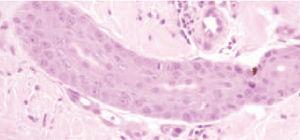

Se realizó una biopsia de tobillo izquierdo, en la que se encontraron cambios dismadurativos en la epidermis con imágenes de atipia celular y degeneración vacuolar en los queratinocitos de la capa basal (fig. 4). En la dermis se observaban algunos infiltrados inflamatorios linfocitarios perivasculares con frecuente extravasación hemática. En los conductos ecrinos existían imágenes focales de siringometaplasia (fig. 5). Se suspendió la administración de metotrexato y se instauró tratamiento con ácido folínico, con lo que se consiguió la resolución de todas las lesiones mucocutáneas.

Fig. 5. Paciente 2. Detalle de la biopsia en la que se observan alteraciones de siringometaplasia escamosa ecrina. (Hematoxilinaeosina, ×100.)